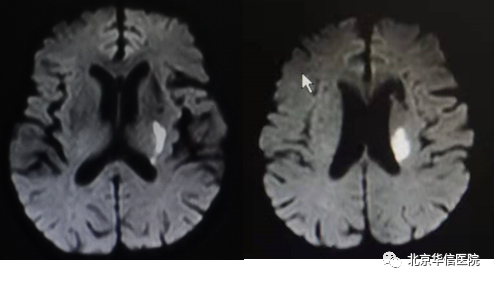

一位79岁男性患者,1年前出现言语不利,右侧肢体无力,伴吞咽困难、饮水呛咳、意识障碍,头核磁共振提示左侧顶叶大面积脑梗塞。患者虽然坚持康复训练,逐渐恢复至可以行走,但右手肌张力逐渐增高,手指远端痉挛呈屈曲状态,无法伸直、持物、执笔等,严重影响了手部功能。充分评估病情后应用肌电引导,精准注射肉毒素至指浅屈肌、指深屈肌、旋前圆肌、拇长屈肌和蚓状肌。患者注射肉毒素1周后右手肌张力逐渐下降,手指可自主伸直,继续配合康复训练,促进手功能的恢复。

第二位是69岁男性患者,5个月前活动中突发右侧肢体无力,且逐渐加重,右侧肢体不能抬离床面,无法独坐、独站,经头核磁共振显示左侧大脑半球多发脑梗塞,积极药物治疗联合综合康复训练后,患者右上肢可抬举,右手无明显抓握,可短时站立,无法独行。神经系统查体发现右上肢肌张力显著增高,前臂旋前屈曲(老百姓形容半身不遂为“胳膊挎筐”或“弹弦子”),站立行走时更显著。应用肌电刺激仪引导精准注射肉毒素治疗上肢痉挛,1周后右上肢肌张力逐渐下降,继续配合康复训练,右上肢可自主伸直,关节活动度及姿势稳定性增加,步态也有改善。